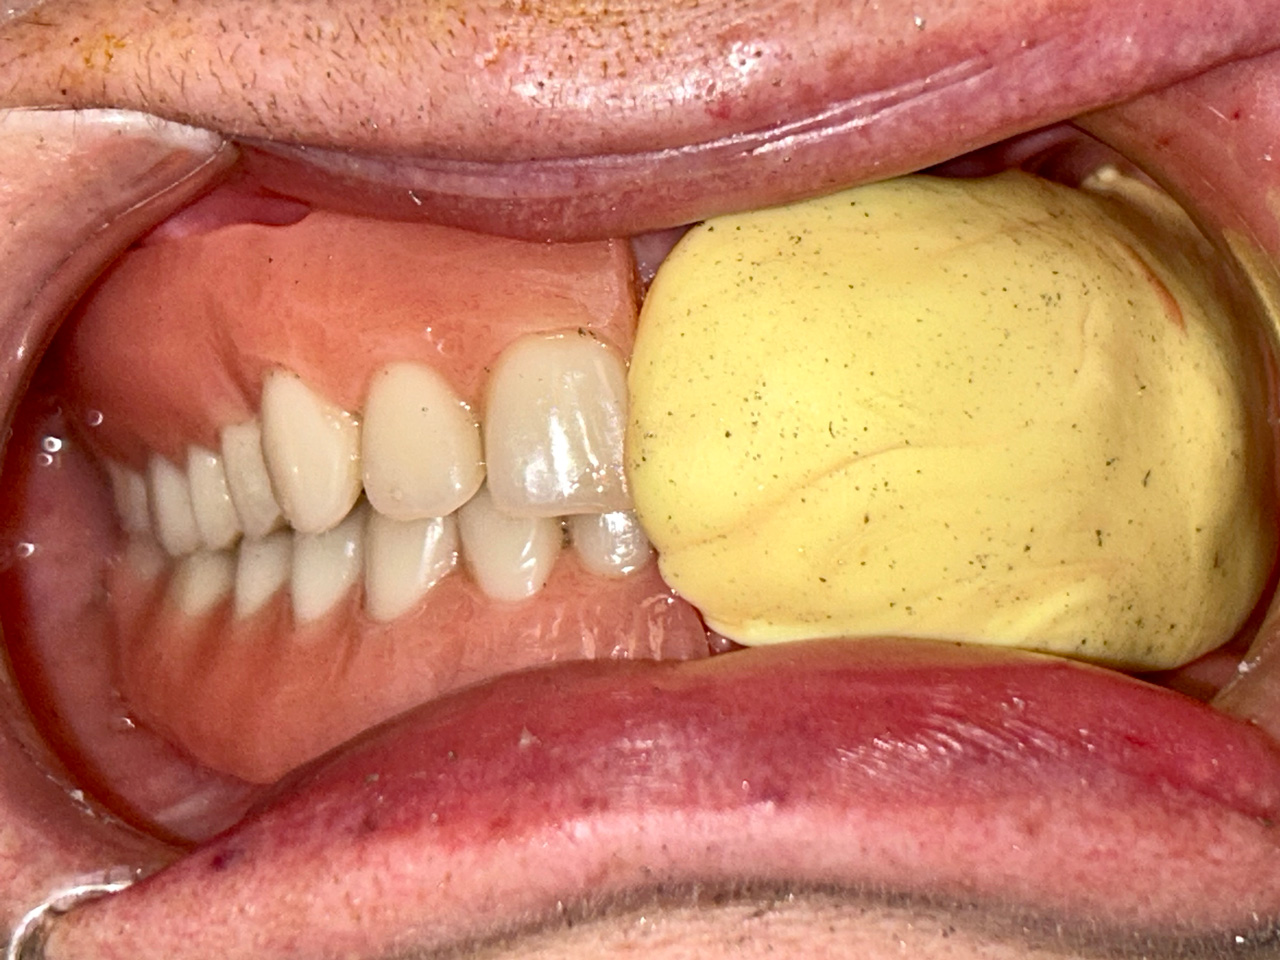

Teljes fogatlanság helyreállítása 2 nap alatt

Teljes fogatlanság helyreállítása 2 nap alatt azonnal terhelhető svájci IHDE implantátumokkal és PMMA műanyag hidakkal. Intraorális szkennerrel vettünk lenyomatot az implantáció után, és erre a digitális mintára készítette el a fogtechnika a hidak digitális tervezését, majd faragta ki műanyagból. Ezt a gyors munkát az azonnal terhelhető implantátumok és a digitális lenyomat, tervezés segítségével tudtuk megcsinálni mindössze 2 nap alatt. Dr. Kelemen Péter és a Symbion Fogtechnika munkája.